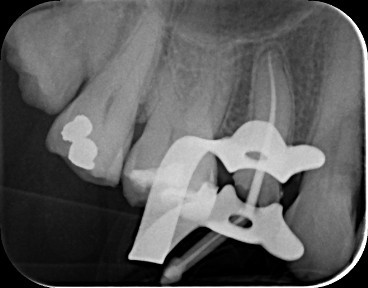

Case 1: Root Canal Treatment UR5